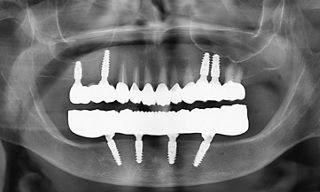

Clinically, she exhibited an edentulous mandible with atrophy and a partially edentulous maxilla (Fig. 2). Radiographic and cone-beam computed tomography (CBCT) evaluation revealed insufficient vertical bone height in the posterior mandible and poor bone quality in both the mandible and posterior maxilla (Fig. 3). The remaining maxillary teeth showed a good prognosis, though some presented carious lesions.

In this region, two tilted and two axial implants were placed freehand. Straumann® Roxolid® SLActive® implants were inserted according to the surgical plan to achieve optimal primary stability. The following implants were placed: #32 – Straumann® BLX Ø3.75 mm, length 10 mm; #35 – Straumann® BLX Ø3.75 mm, length 12 mm; #42 – Straumann® BLX Ø3.75 mm, length 10 mm; and #45 – Straumann® BLX Ø3.75 mm, length 12 mm (Fig. 12).

Implants were placed with a torque of 35 Ncm, which suggests that adequate primary stability was achieved (Fig. 13). The postoperative view showed correct alignment and integration after implant placement, with proper soft tissue adaptation and satisfactory implant positioning in relation to the planned prosthetic restoration (Fig. 14).